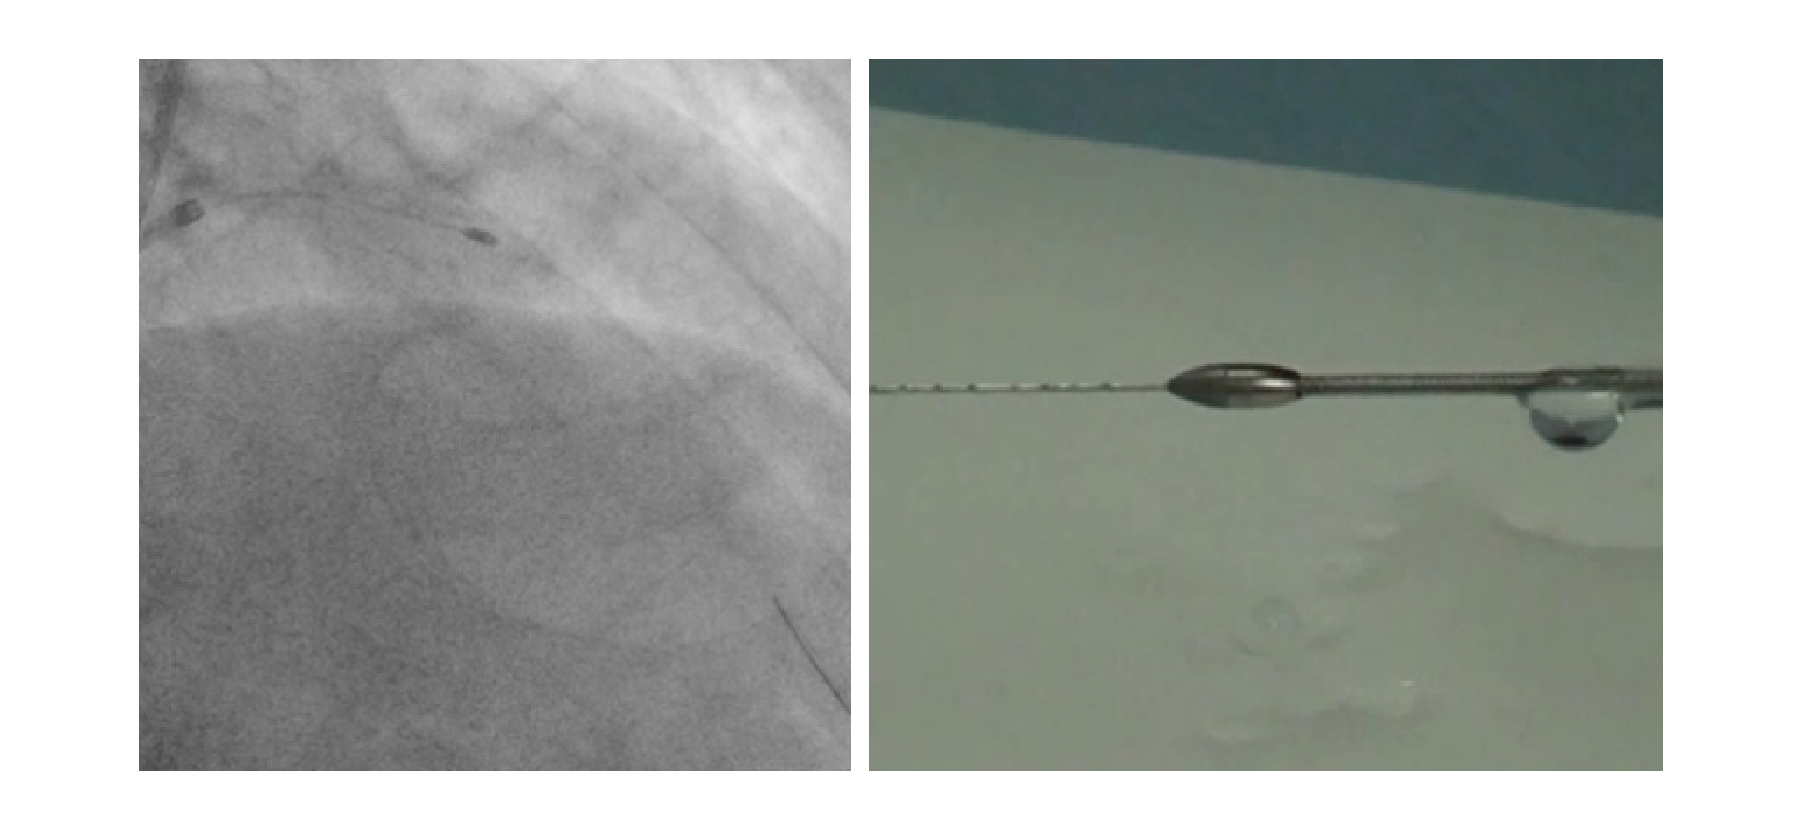

ロータブレーター:先端にダイヤモンドがコーティングされた丸い金属を冠動脈内で回転させることで、石灰化して固くなった血管を削ります。施設基準を満たした病院でのみ使用が可能です。

ダイヤモンドバック:先端から6.5mmのところにクラウンと呼ばれるダイヤモンドで構成された部分があり、クラウンを高速回転させることで、石灰化病変を削ることができます。病変に応じてロータブレーターとの使い分けを行っています。施設基準を満たした病院でのみ使用が可能です。